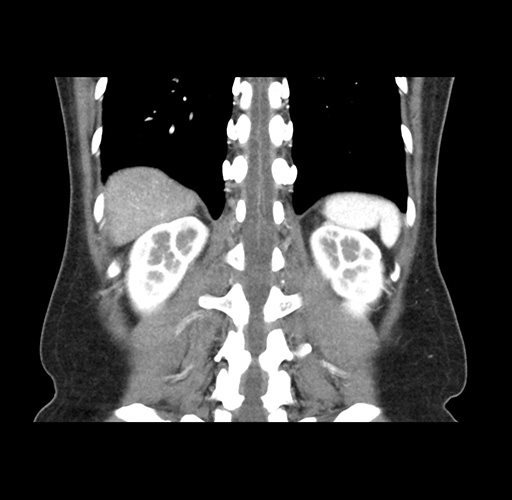

Imaging Analysis

Look through the patient's CT scan to identify any areas of concern for the necessary procedure.

Based on your CT findings, which issue(s) would give reason for "planned slowing down moment(s)" in this case?

Considering a standard left lateral sectionectomy procedure, what step(s) of the operation would you do differently in this case ?